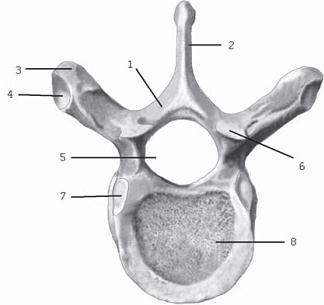

Рисунок № 12. Поясничный позвонок. Вид сверху

1 — позвоночное отверстие; 2 — остистый отросток; 3 — дуга позвонка; 4 — нижний суставной отросток; 5 — верхний суставной отросток; 6 — сосцевидный отросток; 7 — поперечный отросток; 8 — ножка дуги позвонка; 9 — тело позвонка.